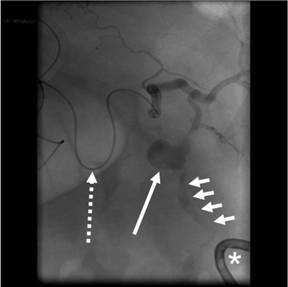

At this point the patient had dropped his blood pressure to 93/53 mmHg. He was resuscitated with i.v. fluids and was transferred to the interventional radiology suite where angiography confirmed active extravasation of contrast from the splenic artery pseudoaneurysm and into the splenic flexure of the colon (Figure 3).

Figure 3. Angiography image with a microcatheter in the splenic artery (interrupted arrow) demonstrates the splenic artery pseudoaneurysm (long arrow) with active contrast extravasation (short arrows) into the colon in close proximity to the percutaneous drain (asterisk). |